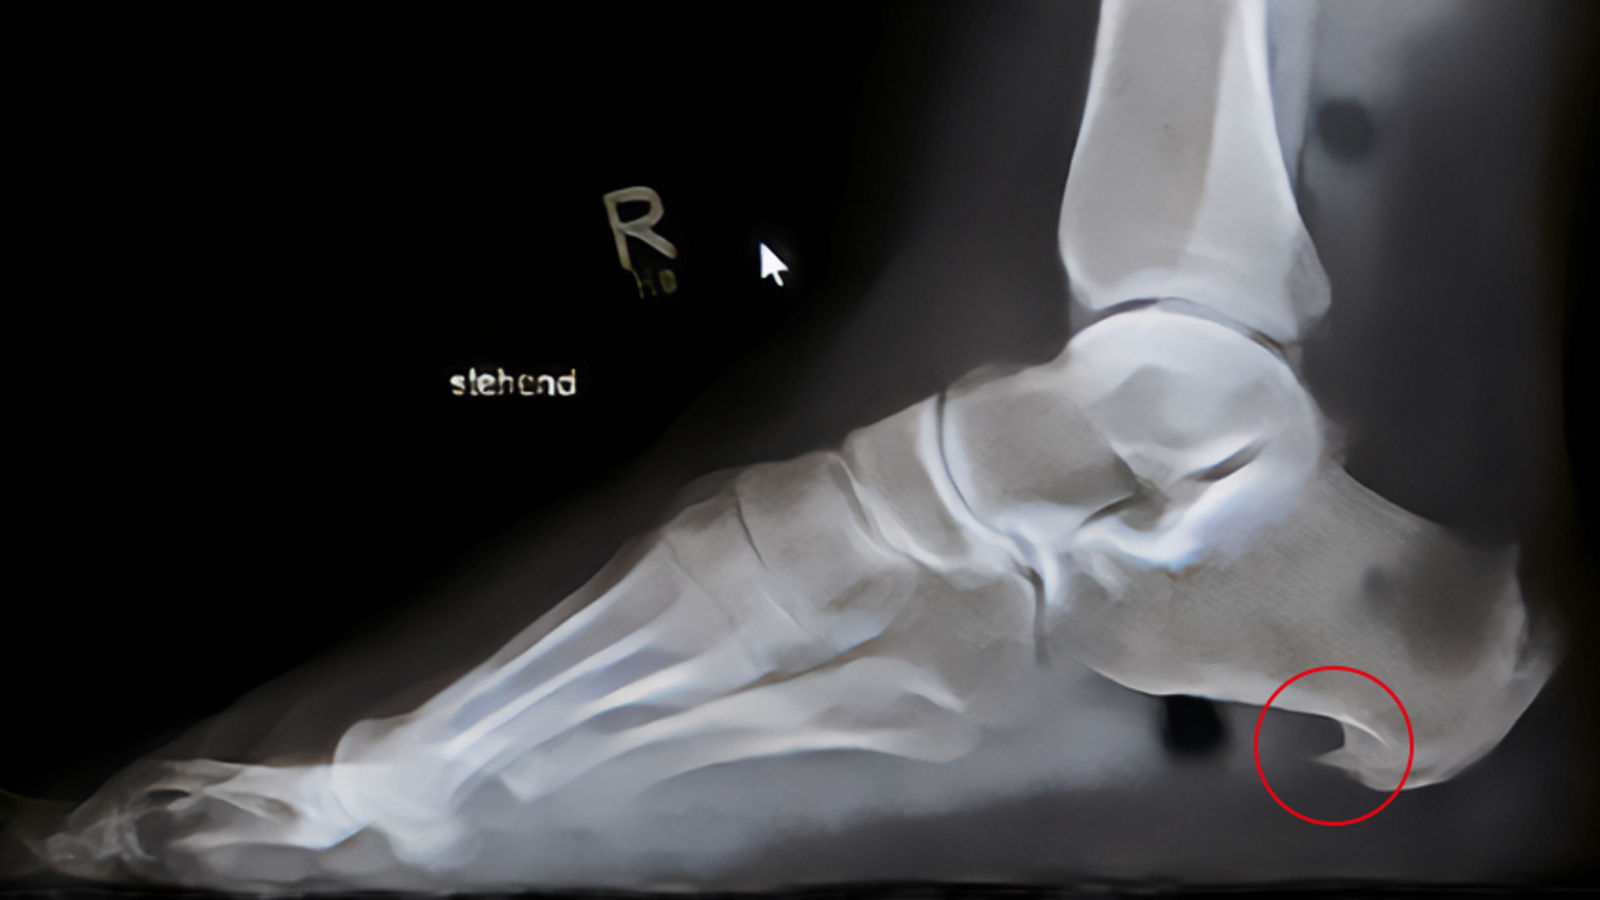

Seitliches Röntgenbild eines Fußes mit Fersensporn

In unklaren Fällen können bildgebende Verfahren eingesetzt werden, wenngleich die Diagnose vornehmlich klinisch gestellt wird. Eine Röntgenaufnahme zeigt sehr zuverlässig, ob ein knöcherner Sporn vorhanden ist. Allerdings muss der - wie schon beschrieben - nicht mit den Beschwerden assoziiert sein. Bei Bedarf wird Ultraschall oder eine Kernspintomografie (MRT) durchgeführt, etwa um Weichteilstrukturen und Entzündungen genauer beurteilen zu können. Falls notwendig, kann eine Fußdruckmessung Aufschluss darüber geben, wie das Körpergewicht beim Stehen oder Gehen verteilt wird und wo es möglicherweise zu Fehlbelastungen kommt.